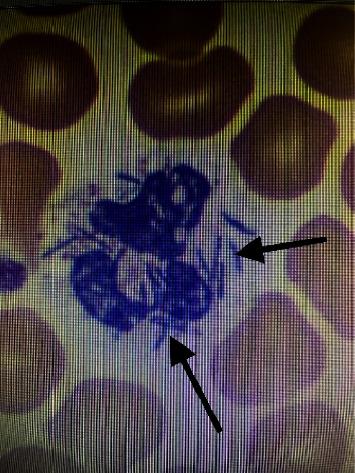

Here, we present a unique case of a 38-year-old male with a history of alcohol use disorder and multiple sexual partners, who presented with fulminant sepsis with shock, multiorgan failure, and livedo racemosa after a dog bite the week prior. The patient was intubated on arrival and was started on vasopressors and antibiotics. Eventually, the patient's clinical status improved, and he was transferred out of the intensive care unit. Blood cultures tested positive for oxidase-positive Gram-negative rods two days after collection, and species identification showed .

在此,我们报告一例独特病例,一名38岁男性,有酒精使用障碍病史且有多个性伴侣,在一周前被狗咬伤后出现暴发性脓毒症伴休克、多器官功能衰竭和网状青斑。患者入院时即行气管插管,并开始使用血管升压药和抗生素。最终,患者的临床状况有所改善,并转出重症监护病房。血培养在采集两天后检测出氧化酶阳性革兰氏阴性杆菌呈阳性,菌种鉴定显示……